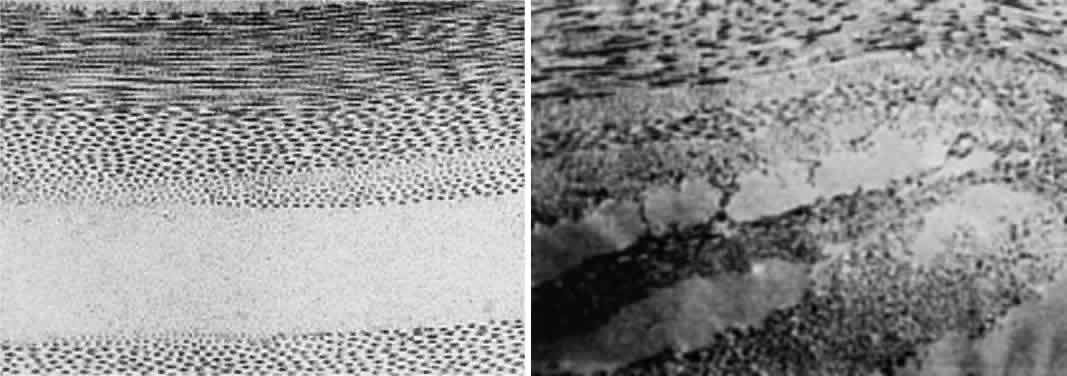

much smaller than a wavelength of yellow light (600 nm).4 Thus, the tiny dimensions and regular arrangement of these fibrils (Fig. 5) account for the minimal scattering.  Fig. 5. Top. Electron micrograph shows the arrangement of collagen fibers in normal

corneal stroma. Bottom. Electron micrograph of a corneal stroma with edema. Note the irregular

collection of fluid. (Miller D, Benedek G: Intraocular Light Scattering. Springfield, IL, Charles

C Thomas, 1973. Courtesy of T. Kuwabara, Howe Laboratory, Harvard

Medical School) Fig. 5. Top. Electron micrograph shows the arrangement of collagen fibers in normal

corneal stroma. Bottom. Electron micrograph of a corneal stroma with edema. Note the irregular

collection of fluid. (Miller D, Benedek G: Intraocular Light Scattering. Springfield, IL, Charles

C Thomas, 1973. Courtesy of T. Kuwabara, Howe Laboratory, Harvard

Medical School)

CORNEAL STROMAL EDEMA In cases of endothelial dystrophy, endothelial trauma, or endothelial incapacitation

due to inflammation (i.e., iritis), the pumping action of the endothelium diminishes and the stroma

takes on additional fluid and thickens. As interfibrillar fluid increases, the

collagen fibers are pushed farther and farther apart. As

the lakes of such fluid exceed one half of a wavelength of light in dimension, light

scattering increases and the cornea takes on a gray appearance (see Fig. 5).4 CORNEAL EPITHELIAL EDEMA In cases of advanced endothelial impairment or acute glaucoma, fluid collects